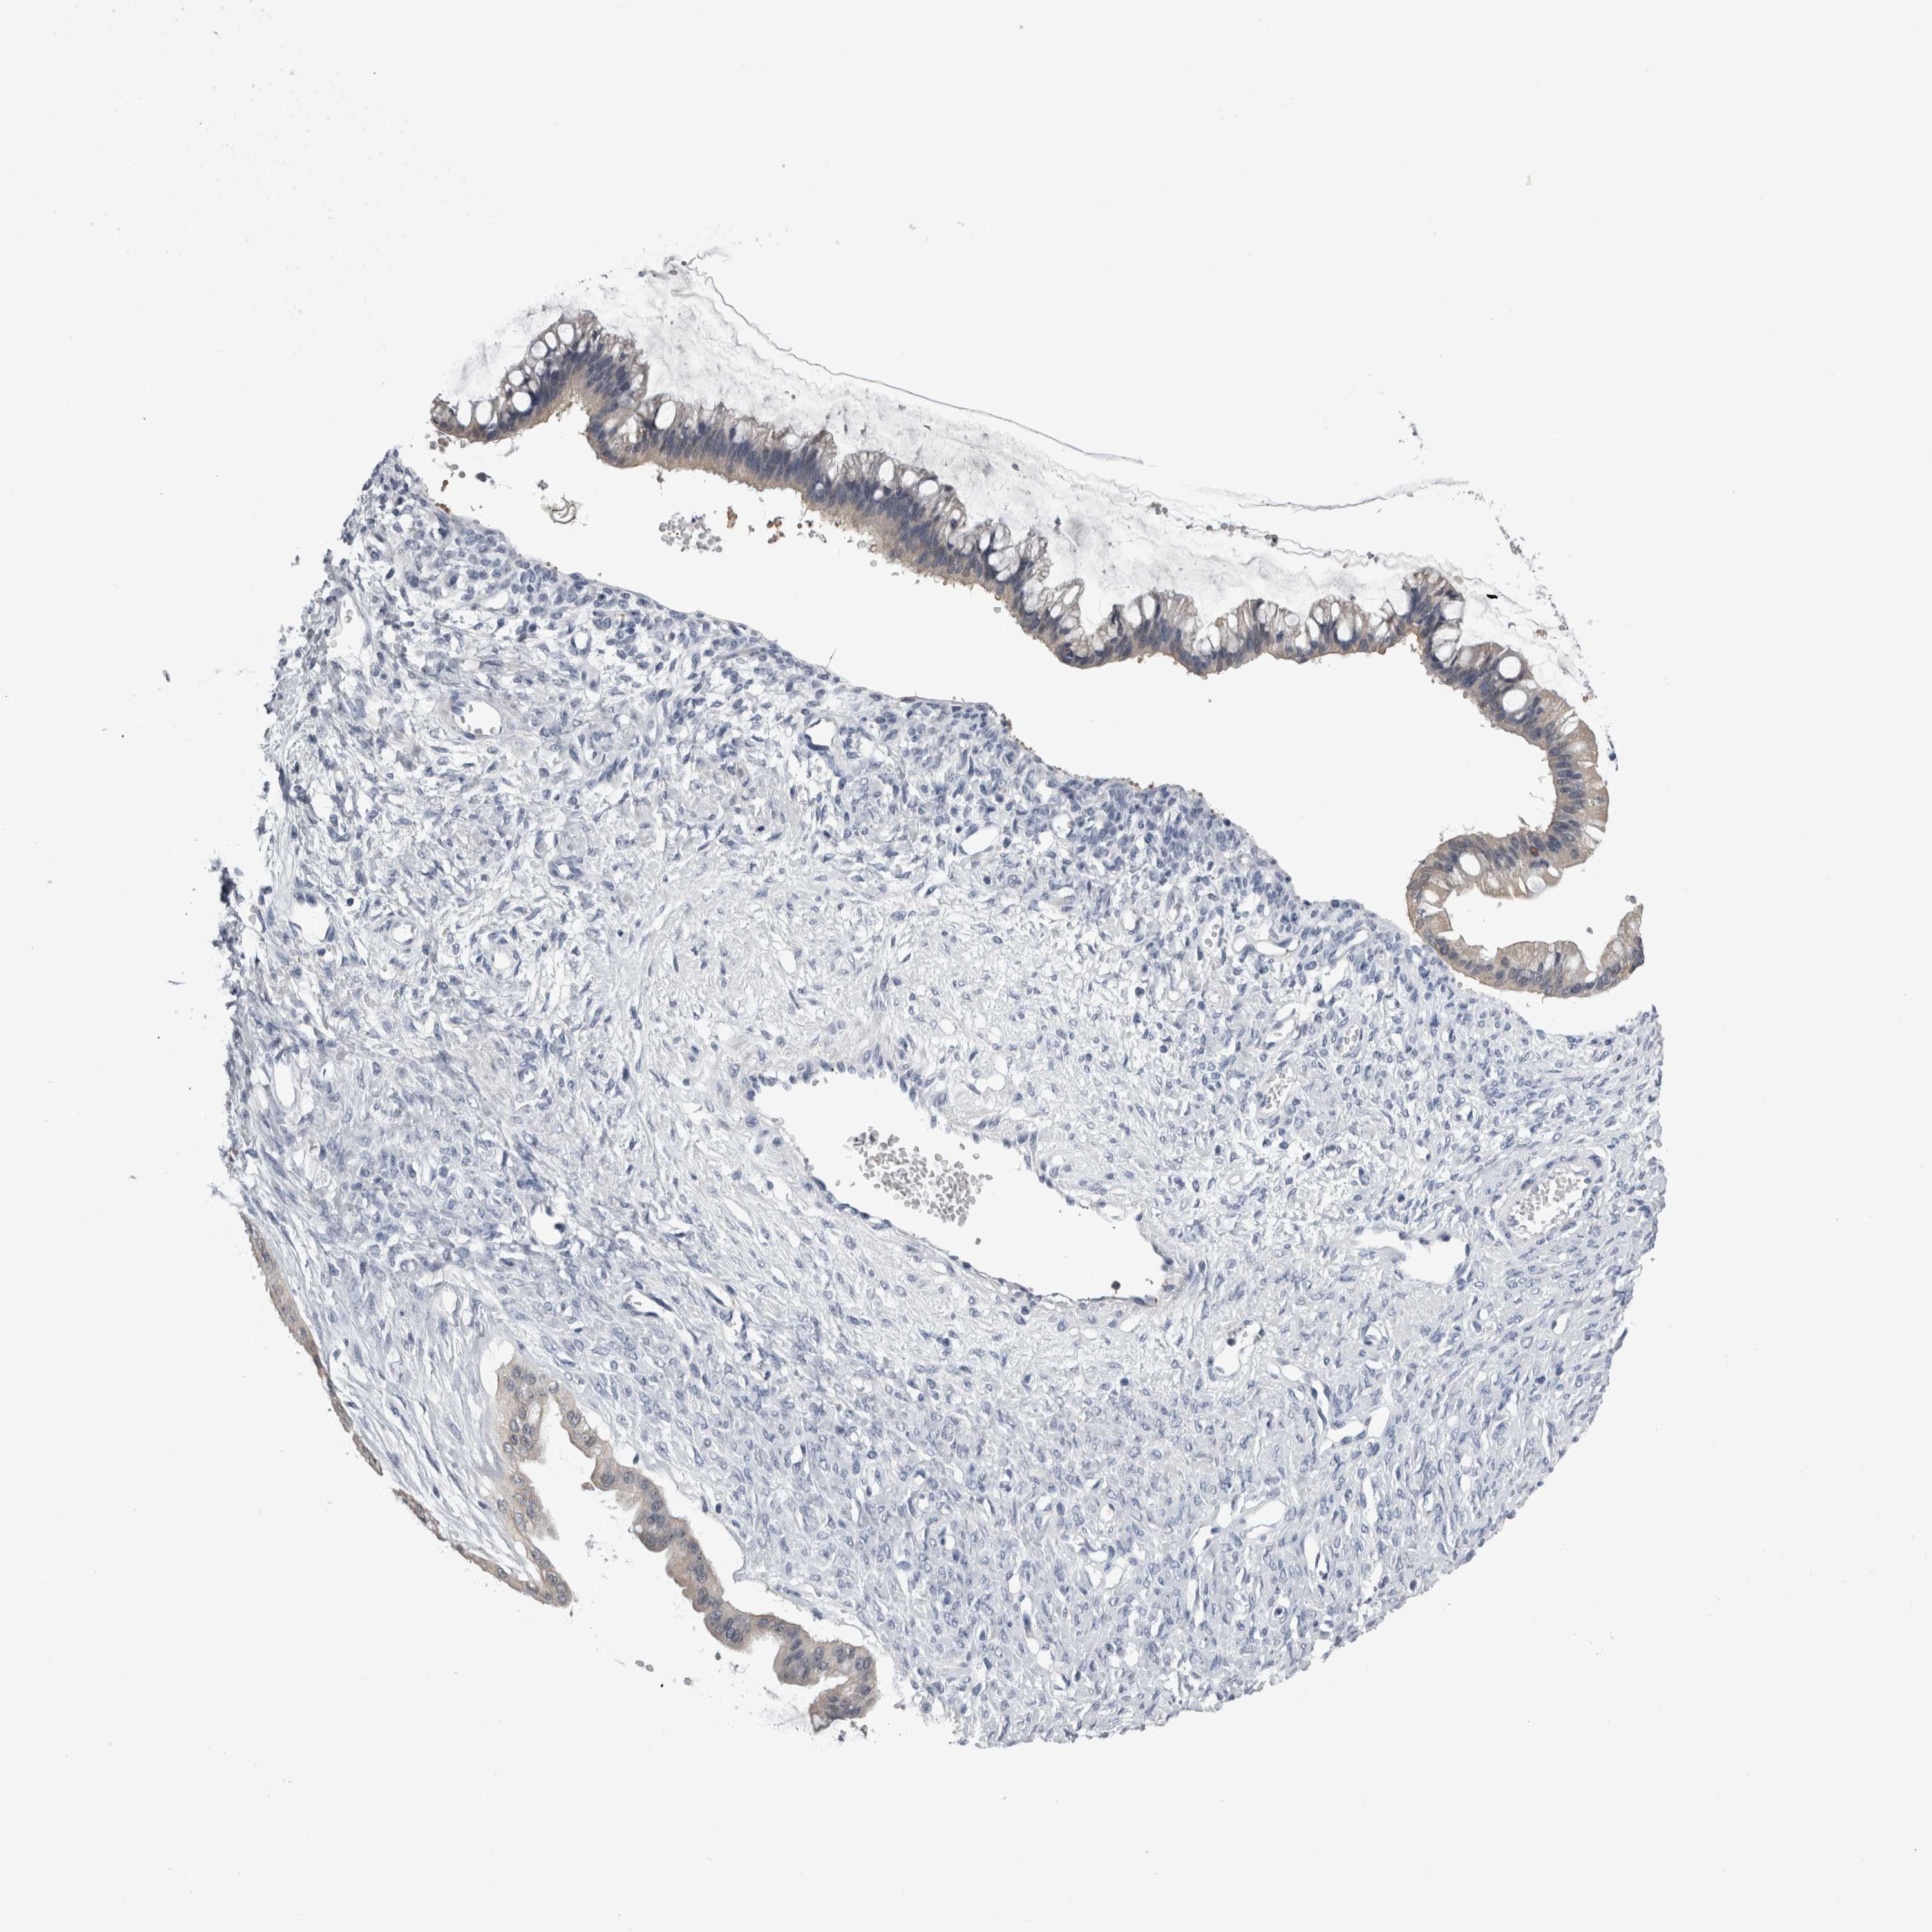

OVARIAN CANCER - Protein expressioni

A mouse-over function shows sample information and annotation data. Click on an image to view it in a full screen mode. Samples can be filtered based on level of antibody staining by selecting one or several of the following categories: high, medium, low and not detected. The assay and annotation is described here.

Note that samples used for immunohistochemistry by the Human Protein Atlas do not correspond to samples in the TCGA dataset.

Antibody stainingi

Antibody staining in the annotated cell types in the current human tissue is reported as not detected, low, medium, or high, based on conventional immunohistochemistry profiling in selected tissues. This score is based on the combination of the staining intensity and fraction of stained cells.

Each image is clickable and will lead to virtual microscopy that enables deeper exploration of all samples and also displays staining intensity scores, fraction scores and subcellular localization as well as patient and tissue information for each sample.

Antibody HPA026292

Antibody HPA055414

Cystadenocarcinoma, serous, NOS

Carcinoma, endometroid

Cystadenocarcinoma, mucinous, NOS

Carcinoma, NOS